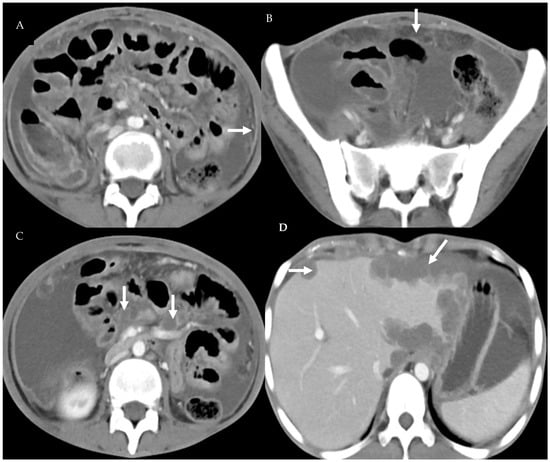

3.4. Peritoneal Involvement

3.5. Predictors of Peritoneal Carcinomatosis